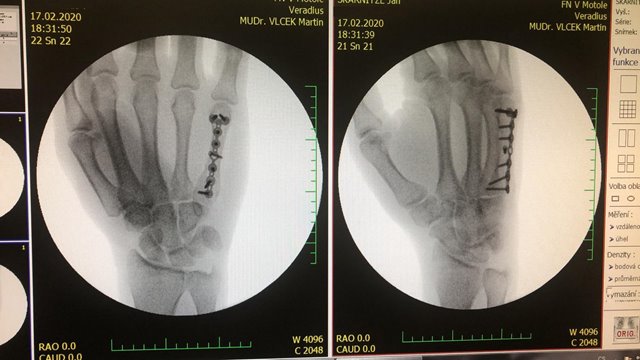

Český reprezentant a olympionik Jan Škarnitzl v pondělí absolvoval plánované vyšetření zlomeniny.

V matacarpu pravé ruky a na základě rozhodnutí lékařského týmu Reprezentace horských kol se ihned podrobil operaci ve Fakultní nemocnici v Motole.

„Vše proběhlo bez problémů, kost je zpevněná dlahou se 7 šrouby, Honzu pravděpodobně pustíme v úterý domů a podle dalších kontrolních vyšetření se domluvíme na formě a postupném návratu zpět do tréninku,“ doplňuje Dr. Jan Kryl.